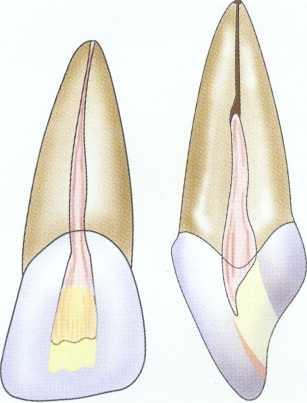

In anterior teeth the clinician must take care to remove all the coronal tissue and debris from the chamber. Material left in the chamber can cause tooth discoloration. The pulp horns are common locations for residual tissue (Figure 2-16).

FIGURE 2-16 A, Residual pulp in horn. B, Tapered, round-ended diamond burs are used to remove debris. The diamond leaves an optimal surface for bonding. C, In immature cases with large pulps, the clinician must take care to remove all material in the pulp horns. Often a tapered, round-ended diamond bur can be used to blend the pulp horns into the access form. This blending should be rechecked before the final restoration because any residual pulpal debris, bacteria, sealer, and guttapercha can contribute to subsequent discoloration.